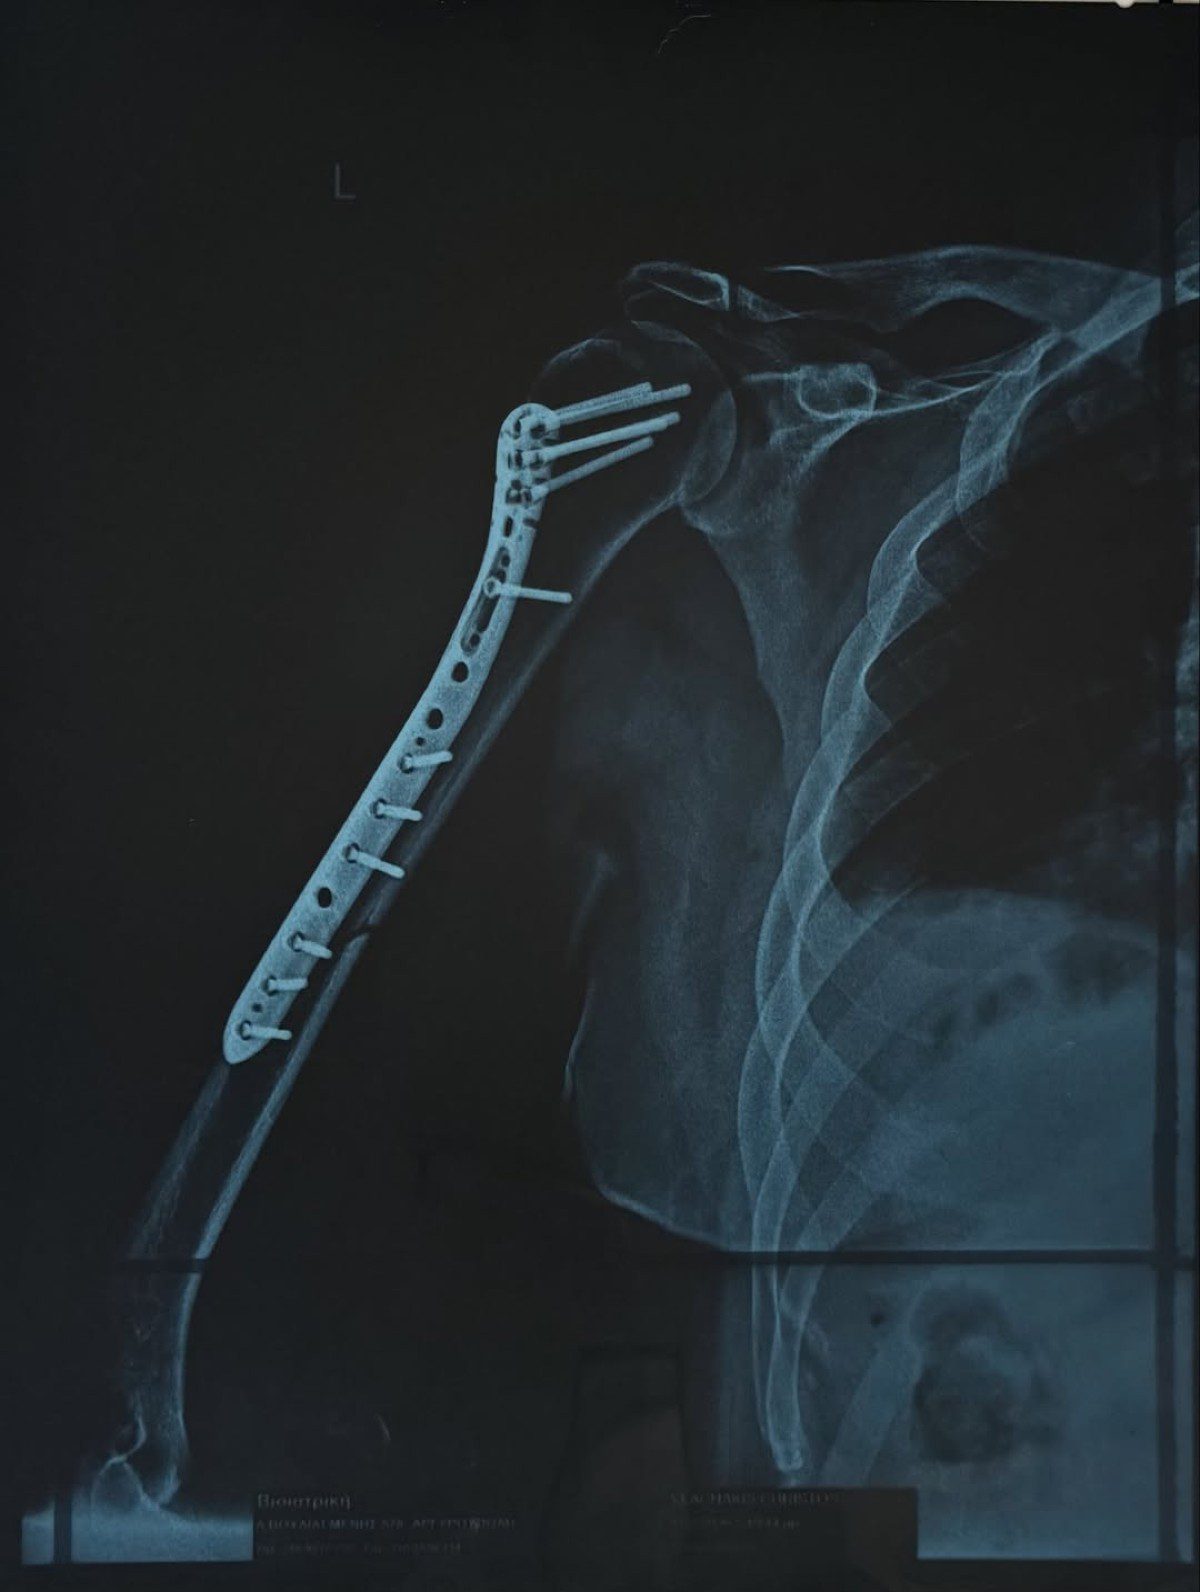

Δύσκολες ώρες πέρασε ο Χρήστος Δάντης, καθώς υπέστη κάταγμα στο χέρι και χρειάστηκε να υποβληθεί σε χειρουργική επέμβαση. Ο γνωστός τραγουδιστής και συνθέτης μεταφέρθηκε στην Ευρωκλινική Αθηνών το βράδυ της Πέμπτης, με την κατάσταση του χεριού του να είναι ιδιαίτερα επιβαρυμένη, όπως περιέγραψε ο ίδιος.

«Όταν θυμάμαι σε ποια κατάσταση μπήκα στην Ευρωκλινική Αθηνών το βράδυ της Πέμπτης, με το χέρι σχεδόν διαλυμένο και σκέφτομαι πόσο γρήγορα θα ανέβω ξανά στη σκηνή την Παρασκευή που έρχεται… μόνο ευγνωμοσύνη μπορώ να νιώσω.

Το «τεράστιο ευχαριστώ» ανήκει στον Χειρουργό Γιώργο Μάζη @shoulderexpert και σε όλο το επιτελείο του, αν και είναι λίγο μπροστά σε αυτό που έκαναν για μένα. Με χειρούργησαν και μου «έδωσαν» πίσω το χέρι μου και τη δυνατότητα να επιστρέψω εκεί που ανήκω: στη σκηνή!», έγραψε στην ανάρτησή του ο Χρήστος Δάντης.

Την ίδια στιγμή, η Ασημίνα Χατζηανδρέου θέλησε να στείλει το δικό της μήνυμα στήριξης. Πριν από λίγες μέρες δημοσίευσε στον προσωπικό της λογαριασμό στο Instagram μια φωτογραφία όπου κρατά τρυφερά το χέρι του Χρήστου Δάντη, γράφοντας: «Σιδερένιος».